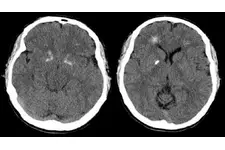

Down sendromu, genetik bir bozukluk olup, genellikle 21. kromozomun üç kopyası bulunmasıyla ortaya çıkar. Anne karnındaki belirtiler, genellikle ultrason incelemeleri sırasında tespit edilebilir. Bu belirtiler arasında, fetal boyutun beklenenden küçük olması, ense kalınlığının artması ve bazı organların gelişiminde anormallikler yer alabilir.

Ultrason incelemeleri, Down sendromunun belirtilerini tespit etmekte önemli bir rol oynar. Özellikle 12. haftada yapılan nuchal translucency (ense kalınlığı) ölçümü, risk değerlendirmesinde kritik bir göstergedir. Eğer ense kalınlığı normalden fazla çıkarsa, genetik danışmanlık önerilebilir. Bunun yanı sıra, fetal kalp anormallikleri ve diğer fiziksel gelişim sorunları da ultrason ile gözlemlenebilir.